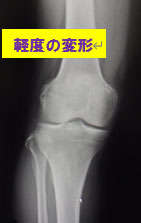

①変形性ひざ関節症などは有名ですが(下図)